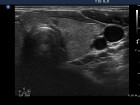

Ultrasonography: Both lobes were enlarged, moderately hypoechogenic, inhomogeneous and displayed increased vascularization.

2. Note the relation between volume, echogenicity, vascularization and hormone levels.